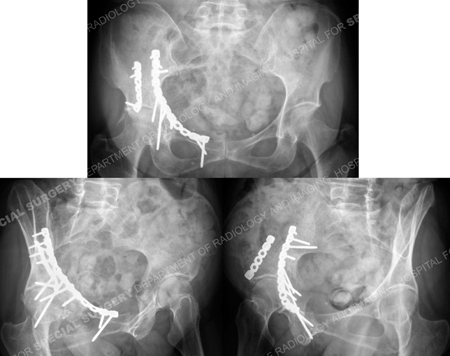

Radiographs 9 years following surgery demonstrating an excellent result with maintenance of reduction.